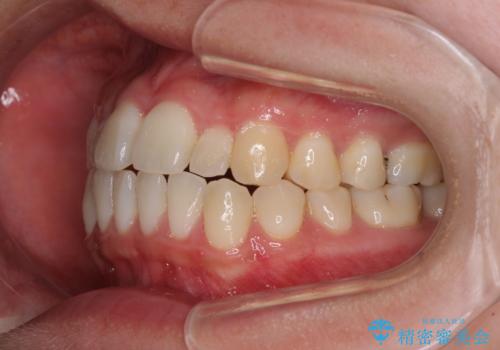

すきっ歯とオープンバイトをインビザラインで改善

- 前歯の上下スペースと前歯の隙間を気にして来院された患者様です。

インビザラインにより上下の前歯の隙間を閉じていくこととしました。

上下の隙間に舌が入り込むことが、すきっ歯やオープンバイトの原因であったため、舌の筋肉のトレーニングも並行して行い、後戻りの抑制を図りました。